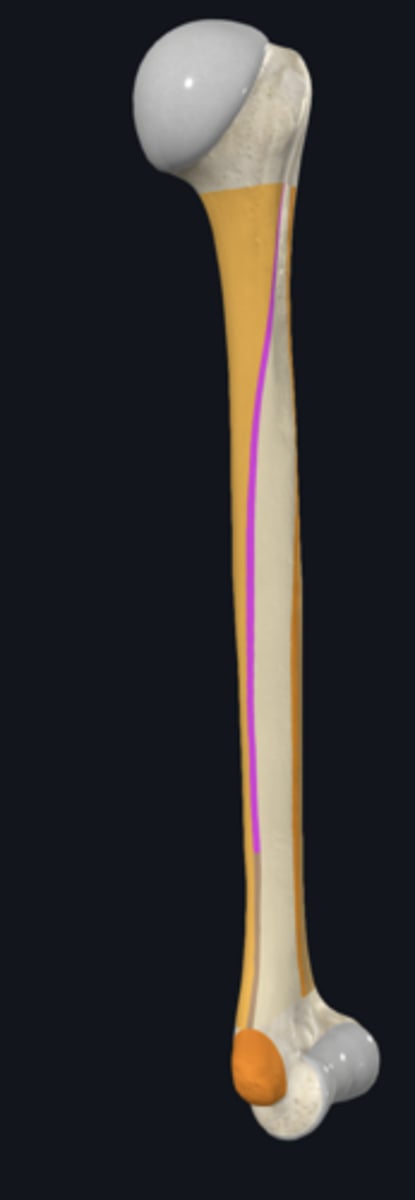

anatomical neck of humerus

body of humerus

condyle of humerus

greater tubercle

head of humerus

lesser tubercle

anterior border of humerus

lateral border of humerus

lateral supracondylar ridge

medial border of humerus

medial supracondylar ridge

posterior surface of humerus

deltoid tuberosity

radial groove

surgical neck of humerus